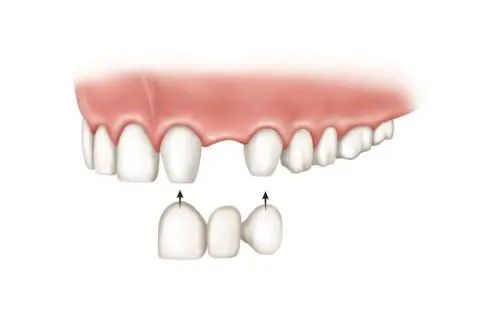

02 - 固定局部义齿

又称为固定桥,由固位体(A)和桥体(B)、连接体(C)组成。暂且可以把拔牙的地方想象成一条河,修复它就相当于建一座桥,那么桥墩就是缺失牙两侧的牙齿,套在桥墩上的部件称为固位体,桥体就是缺失牙位置的修复体。

固定桥修复一般需要在拔牙后3个月进行,治疗时长一般在1个月内,医患双方沟通好方案后,开始选择颜色、牙体预备、制作牙齿的模型、做临时牙、送加工厂制作、戴牙。

向左滑动查看固定义齿修复,慎滑(图片来源于必应)